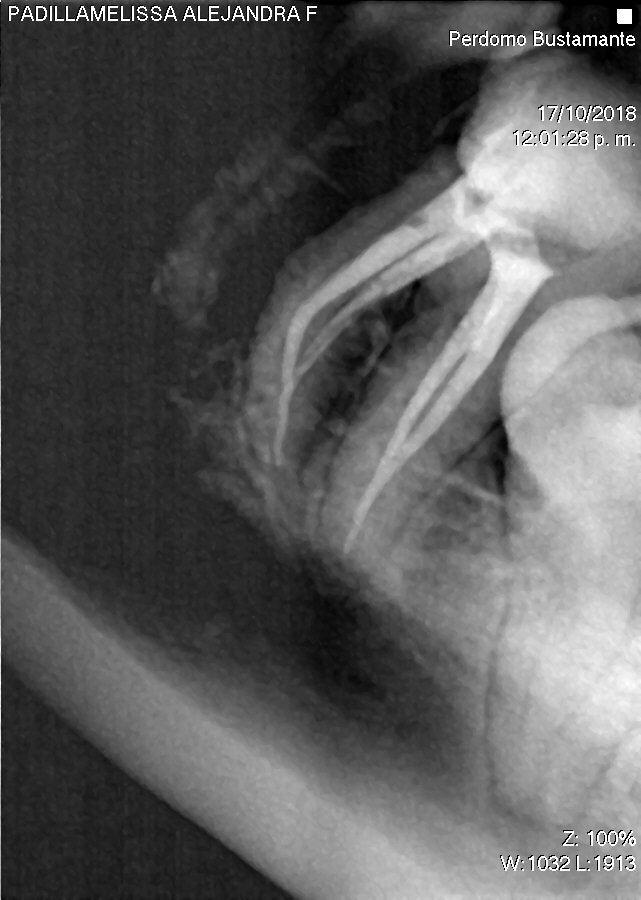

Endodoncia Finaliza Primer Molar Superior